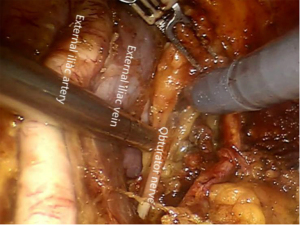

U type of dissection of pelvic lymph node

Pelvic lymph node dissections are always the center of the surgery. After the resection of the lymph nodes from the lateral side of the external iliac vessel to the foot, the internal iliac vessels and the external iliac vessels were identified and exposed. The space between the obturator fossa and the lateral external iliac vessel was widened by blunt dissection, carefully exposing the obturator nerve and the vessel network below it, and gradually remove the pelvic lymph nodes. We called it U type dissection (Figure 4).